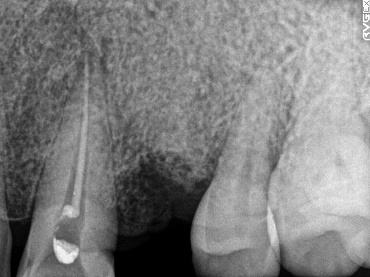

レントゲンで詳しく診てみると、歯根が真っ二つに割れていることがわかりました。臭いは、割れているために炎症を引き起こし、そこからの膿が原因でした。保存することができず抜歯しました。抜歯後、インプラントを埋入しました。

所感

抜歯後、ブリッジ、部分入れ歯の選択肢もありましたが、2013年に右下にインプラント治療をし、インプラントの良さを十分に理解しておられましたので、今回も1本歯を失ったところにインプラント治療を希望されました。歯根破折が原因で抜歯になった方ですので、もしブリッジにしていたら再度歯根の破折を引き起こし、さらに歯を失う可能性が、高い方でした。インプラントは、それ自身が単体で植立し、単独で咬合力を負担します。ブリッジや部分入れ歯のように他の歯に歯がない部分の負担を負わせることがないので、他の歯を守ります。インプラントにして正解だと考えます。今回もX-Guideを使った埋入で、安心安全に行うことができました。

Before

歯根が真っ二つに割れていました

抜いた歯

【抜歯後】

After